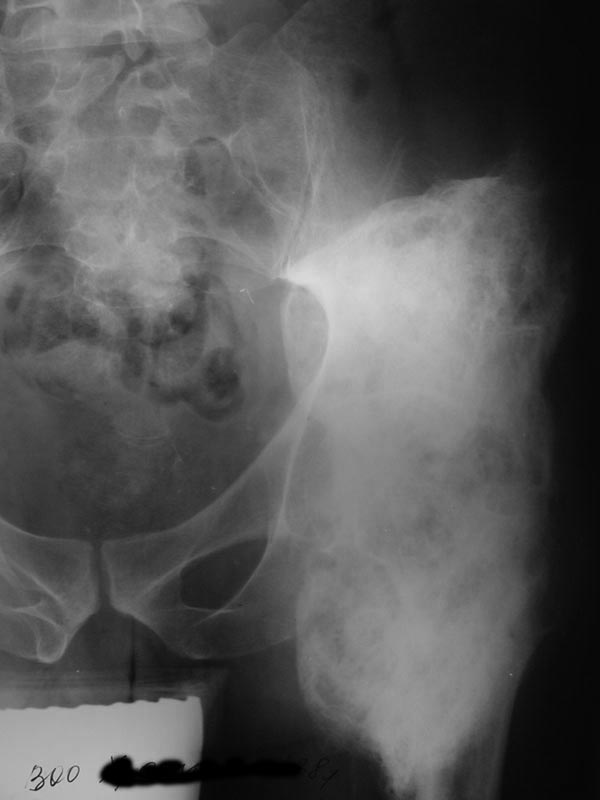

Мужчина 38 лет, Х.В.Н., диагноз: Закрытый травматический компрессионно-оскольчатый перелом L1 позвонка, вывих Тh 12, ушиб, сдавление спинного мозга, нижняя параплегия, нарушение функции тазовых органов. Операция 01.07.03: ламинэктомия Th 12-L1, задний спондилодез проволокой с протакрилом.06.11.03 -- удаление протакрила, ламинэктомия Th 12-L1, декомпрессия спинного мозга, менингомиелолиз.У больного, как проявление нейродистрофического синдрома, сформировались грубые оссификаты вокруг обоих тазобедренных суставов с резким ограничениемдвижений.14.01.04 – операция иссечения переднебоковых оссификатов правого тазобедренного сустава. На операции достигнуто сгибание около 85 град. Впослеоперационном периоде потеря коррекции значительна (более 50%).На сегодняшний день: Больной лежит, движения в тазобедренных суставах отсутствуют. По передней поверхности обоих суставов пальпируются плотныеопухолевидные образования 6 х 8 см.На R-граммах: обширные оссификаты по передней и боковой поверхности т/бедренных суставов (см. приложенные файлы).Планируется оперативное лечение: иссечение оссификатов.Больного необходимо посадить в кресло-каталку для дальнейшей реабилитации.У кого есть предложения?Направление пациента на лечение согласовано с Министерством здравоохранения Хабаровского края, финансирование обещано.Лечащий врач Е.В.Квитченко